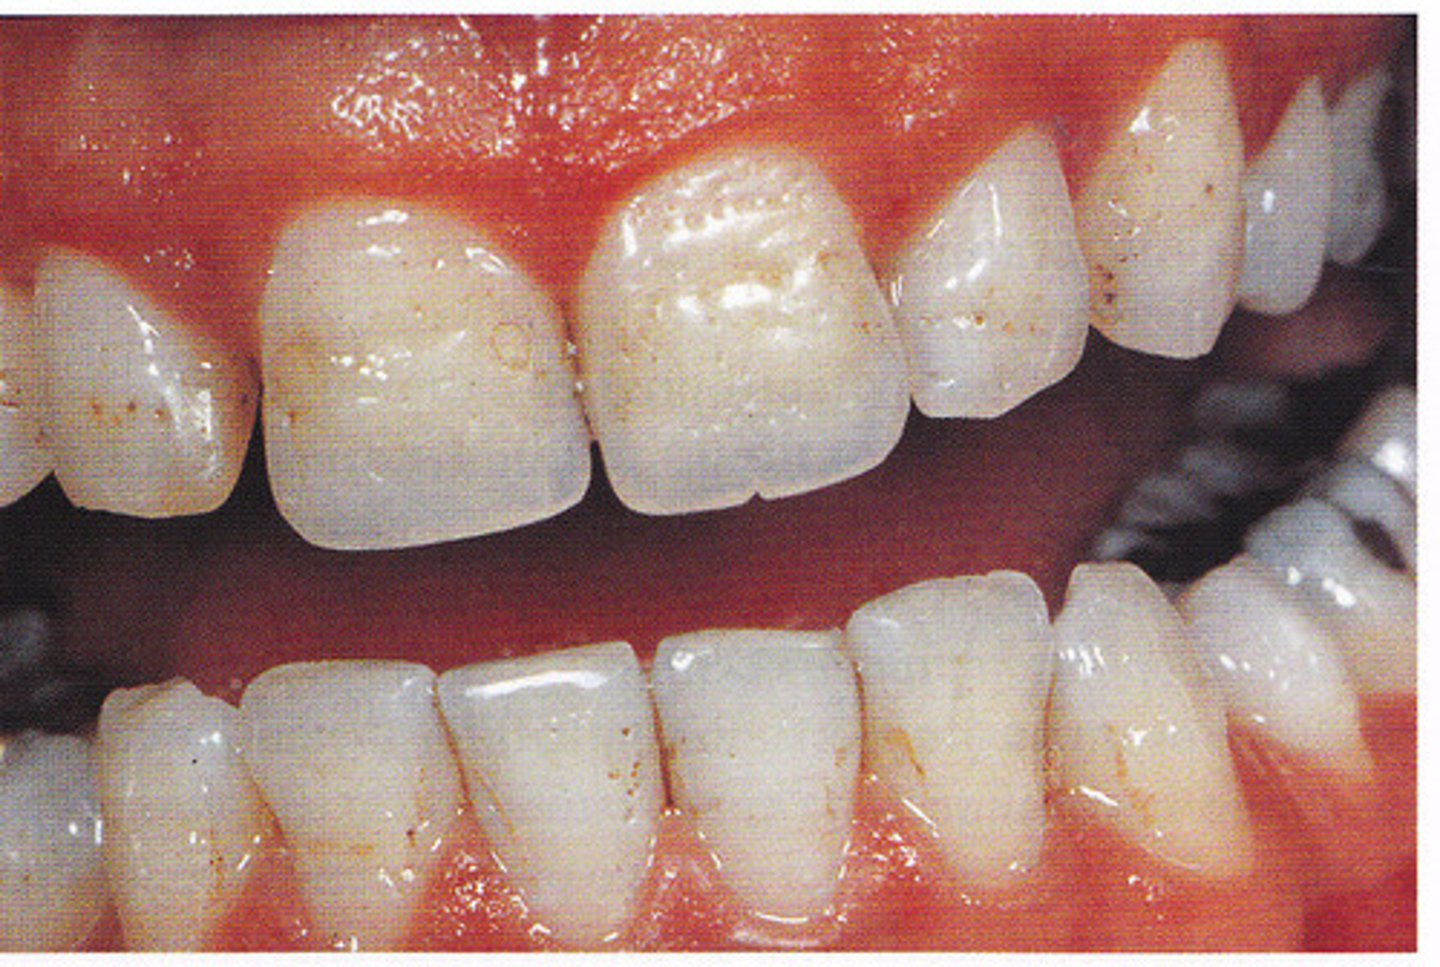

What are the clinical features of hypomaturation AI?

-normal amount of enamel

-decreased mineralization → abnormal crystallization (enamel rods don't form)

-harder than dentin

-radiodensity like dentin

-mottled - white/brown/yellow → "snow-capped" (white cusp tips)

-normal shape at eruption → enamel chips off of dentin